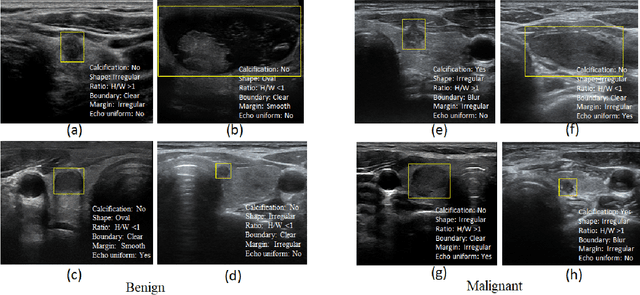

Abstract:Ultrasound (US) is the primary imaging technique for the diagnosis of thyroid cancer. However, accurate identification of nodule malignancy is a challenging task that can elude less-experienced clinicians. Recently, many computer-aided diagnosis (CAD) systems have been proposed to assist this process. However, most of them do not provide the reasoning of their classification process, which may jeopardize their credibility in practical use. To overcome this, we propose a novel deep learning framework called multi-attribute attention network (MAA-Net) that is designed to mimic the clinical diagnosis process. The proposed model learns to predict nodular attributes and infer their malignancy based on these clinically-relevant features. A multi-attention scheme is adopted to generate customized attention to improve each task and malignancy diagnosis. Furthermore, MAA-Net utilizes nodule delineations as nodules spatial prior guidance for the training rather than cropping the nodules with additional models or human interventions to prevent losing the context information. Validation experiments were performed on a large and challenging dataset containing 4554 patients. Results show that the proposed method outperformed other state-of-the-art methods and provides interpretable predictions that may better suit clinical needs.